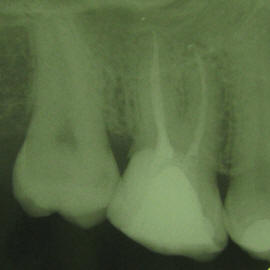

V zelo redkih primerih, endodontsko zdravljenje ne more biti uspešno izvedeno zaradi zelo tenkih in ukrivljenih kanalov ali slabega prejšnjega endodontskega zdravljenja

Slabo endodontsko zdravljenje

Nekateri od teh primerov se uspešno rešujejo z revizijo (ponovno čiščenje in razkuževanje kanalov) ali z apikotomijo (kirurško odstranitvijo vrška korenine).

Po ponovnem zdravljenju koreninskih kanalov